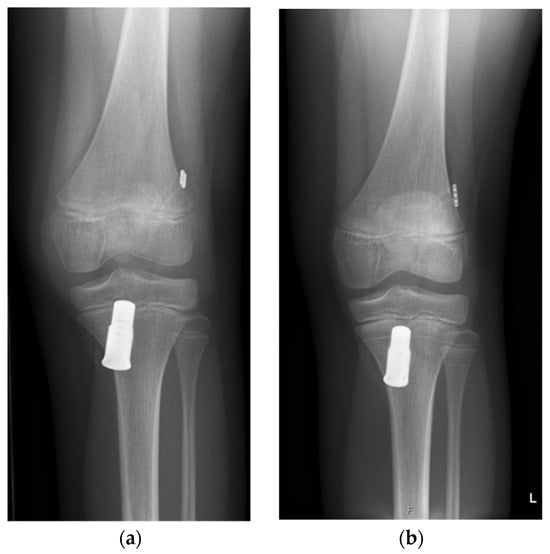

In a diagnostic arthroscopy, the ACL injury and concomitant lesions were confirmed. In case of a meniscal tear, the meniscus was repaired first, before taking care of the ACL. The torn ACL was prepared with shuttle sutures (2-0 PDS, Polydioxanon) depending on the localization of the rupture: In proximal ruptures, the proximal end of the ACL was prepared with shuttle sutures; in case of intraligamentary lesions, both stumps were sutured. The next step was drilling the respective tibial and femoral tunnels (10 mm and 6 mm) according to conventional ACL reconstruction techniques. On the tibial side, the Ligamys Monobloc holding the spring screw mechanism was inserted. Depending on the age and size of the child, the screw had to be placed through the physis. As mentioned above, in case of intraligamentary lesions, several sutures to the femoral or tibial stump were needed to align the ACL. Finally, a polyethylene braid (1.8 mm) was shuttled from the femoral side through the Ligamys Monobloc on the tibial side. The polyethylene braid was then fixed with an Endobutton, together with the shuttle sutures from the ACL stump on the femoral side. The polyethylene braid was tensioned in the Ligamys screw with a continuous tension of 30–50 N over the entire range of motion of the knee on the tibial side. The polyethylene braid, therefore, prevents anterior tibial translation and distraction of the ACL stumps during the healing phase of the realigned ACL in the first three months postoperatively. Microfracturing of the femoral footprint supports the self-healing process of the ACL. Figure 1 shows the radiograph of an implanted Ligamys system in an 11-year-old girl with screw placement through the physis. All surgeries were performed by the same pediatric orthopedic surgeon (author K.Z.) under the guidance of one of the originators of the technique (author S.K.).

Figure 1.

Anterior–posterior radiographs of a knee of an eleven-year-old girl who underwent dynamic intraligamentary stabilization repair. (a) Initial postoperative radiograph; (b) one year postoperative: Due to the growth of the patient (symmetric Harris growth line), the Ligamys screw is now located more distally. The physis of the proximal tibia is still open.